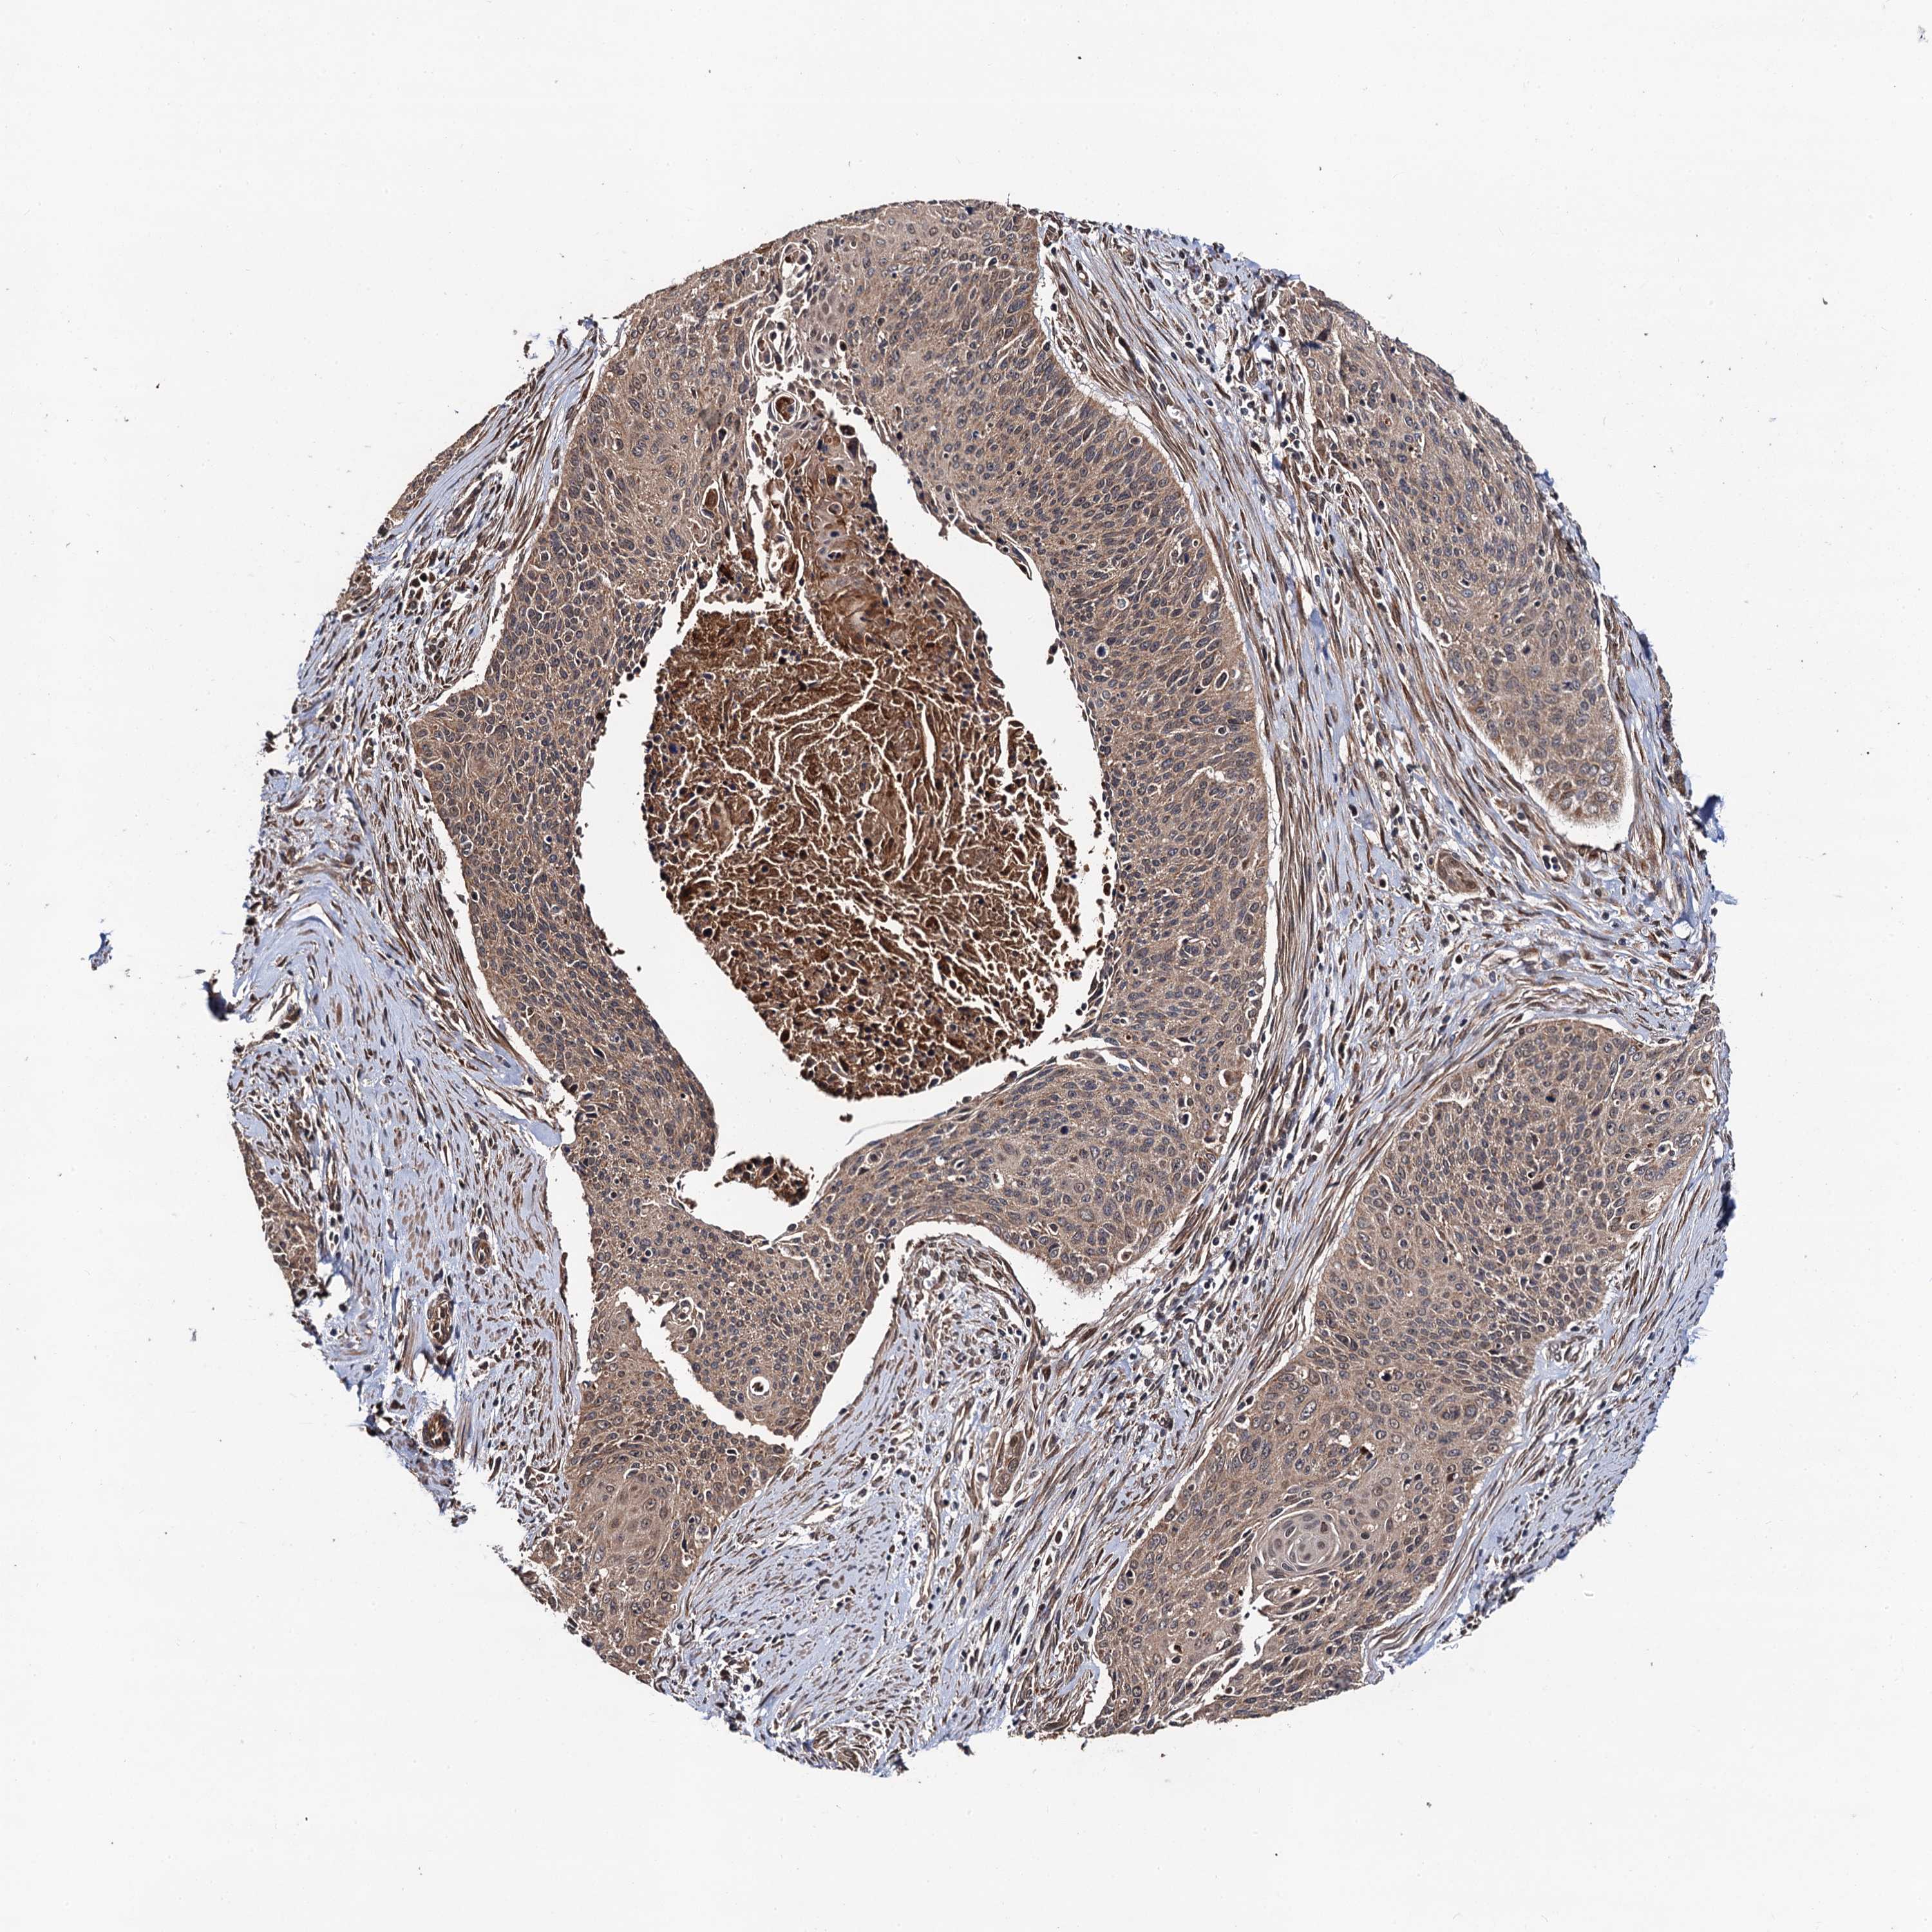

CERVICAL CANCER - Protein expressioni

A mouse-over function shows sample information and annotation data. Click on an image to view it in a full screen mode. Samples can be filtered based on level of antibody staining by selecting one or several of the following categories: high, medium, low and not detected. The assay and annotation is described here.

Note that samples used for immunohistochemistry by the Human Protein Atlas do not correspond to samples in the TCGA dataset.

Antibody stainingi

Antibody staining in the annotated cell types in the current human tissue is reported as not detected, low, medium, or high, based on conventional immunohistochemistry profiling in selected tissues. This score is based on the combination of the staining intensity and fraction of stained cells.

Each image is clickable and will lead to virtual microscopy that enables deeper exploration of all samples and also displays staining intensity scores, fraction scores and subcellular localization as well as patient and tissue information for each sample.

Antibody HPA066153

Adenocarcinoma, NOS